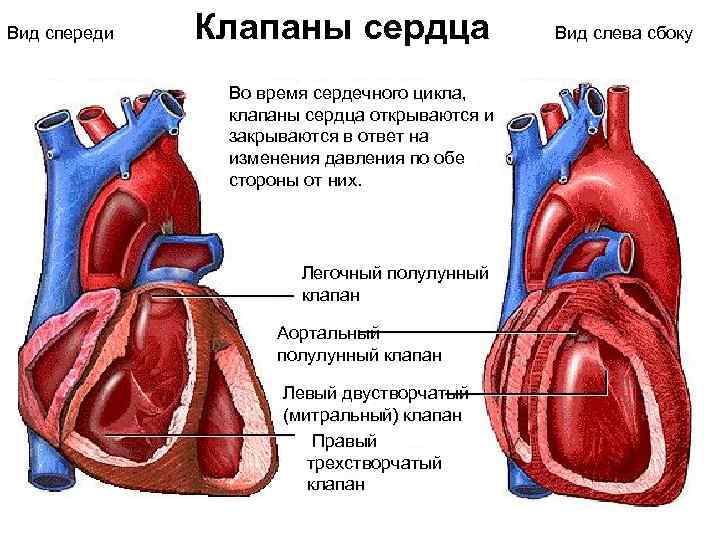

Вид спереди Клапаны сердца Во время сердечного цикла, клапаны сердца открываются и закрываются в ответ на изменения давления по обе стороны от них. Легочный полулунный клапан Аортальный полулунный клапан Левый двустворчатый (митральный) клапан Правый трехстворчатый клапан Вид слева сбоку

Вид спереди Клапаны сердца Во время сердечного цикла, клапаны сердца открываются и закрываются в ответ на изменения давления по обе стороны от них. Легочный полулунный клапан Аортальный полулунный клапан Левый двустворчатый (митральный) клапан Правый трехстворчатый клапан Вид слева сбоку